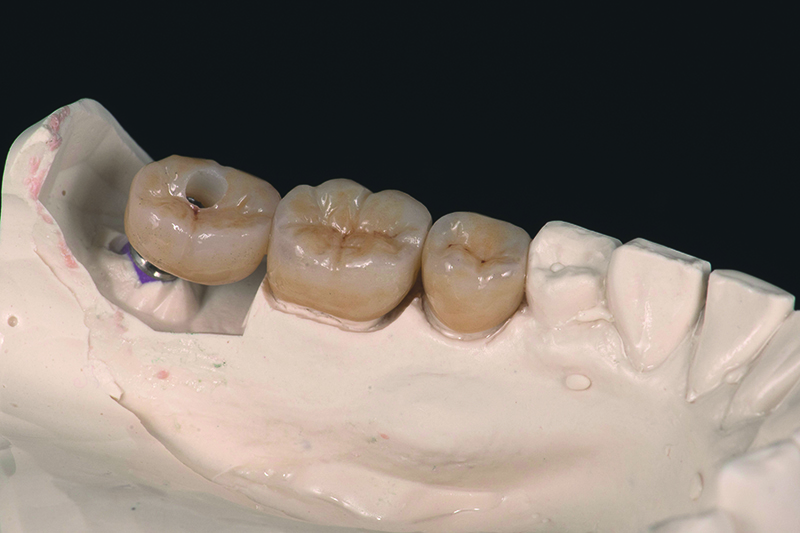

Cas clinique avec Initial™ LiSi Block

Initial™ LiSi Block (poli)

Initial™ LiSi Block (avec maquillage et glazure)